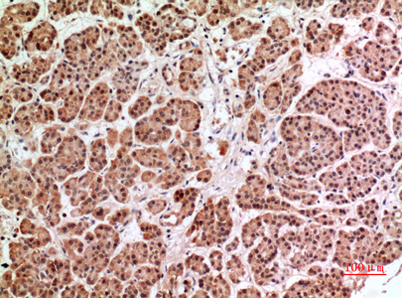

Product name: HPA1 rabbit pAb

Dilutions: Western Blot: 1/500 - 1/2000. IHC-p: 1/100-1/300. ELISA: 1/20000. Not yet tested in other applications.

Immunogen: The antiserum was produced against synthesized peptide derived from the Internal region of human HPSE. AA range:241-290